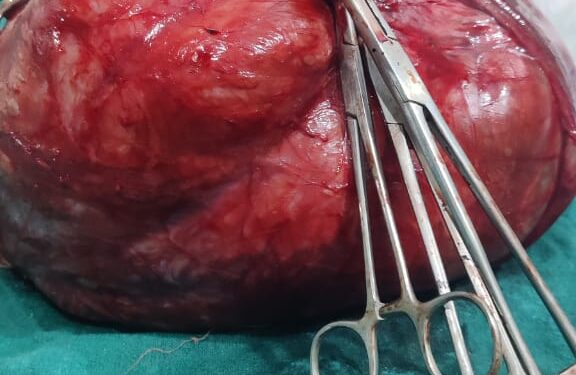

पटना।दर्द से तड़प रही महिला जब अस्पताल पहुंची तो डॉक्टर ने उसका ऑपरेशन कर पेट से 15 किलोग्राम का ट्यूमर निकाला।पन्द्रह किलोग्राम का ट्यूमर देखकर डॉक्टर भी सकते में आ गए।हालांकि डॉ समानता और उनकी टीम ने दो घंटे की कठिन सर्जरी कर महिला की जान बचा ली है।बताया जा रहा है कि पटना जिले की रहने वाली महिला के पेट से डॉक्टरों की टीम ने सफल सर्जरी करके 15 किलोग्राम का ट्यूमर निकाला है।

दोे घंटे की सर्जरी के बाद महिला के गर्भाशय से ट्यूमर निकालकर डॉक्टरों ने उसे नई जिंदगी दी है।डॉक्टरों ने कहा कि अगर समय रहते ट्यूमर नहीं निकाला जाता तो महिला की जान नहीं बचायी जा सकती थी।वैसे महिला फिलहाल डॉक्टरों की निगरानी में रहेगी।हिमालया हॉस्पिटल पटना एक बार फिर अपने चिकित्सीय उपलब्धि के कारण चर्चा में है।बताया जा रहा है कि 45 वर्षीय महिला का वजन धीरे धीरे बढ़ रहा था।इतना ही नहीं,महिला को पेट में कुछ गोला जैसा आभास हो रहा था।महिला को यह भी लग रहा था कि मोटापा के कारण ऐसी दिक्कत हो रही है।जिस दौरान पीरियड्स में भी परेशानी आ रही थी।

तब जाकर महिला हिमालया हॉस्पिटल में डॉक्टर समानता से दिखवाने के लिए आयी।जहां देखने के बाद पता चला कि पेट में बहुत बरा ट्यूमर हैं।जिसकी जांच करवायी गयी।जांच के तुरंत बाद सर्जरी का प्लान किया गया।बता दें कि युटरस के उपर से निकला हुआ ट्यूमर था।जिस वजह से यूटरस और ट्यूमर दोनों को निकाला गया।सर्जरी के बाद डॉ समानता ने बताया कि अगर समय से ऑपरेशन नहीं होता तो यह ट्यूमर कभी भी अदंर फट सकता था और महिला की जान भी जा सकती थी।फिलहाल, महिला सात दिन तक डॉक्टरों की निगरानी में रहेगी।